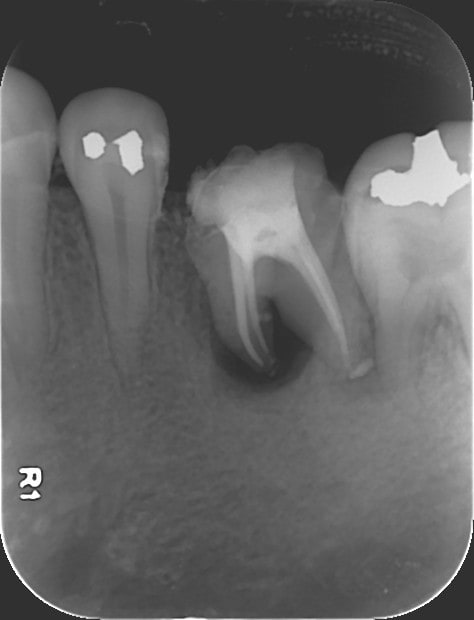

1   02022015 xhyug0 - Eugenol

3   02022015 athoja - Eugenol

2   02022015 jomvv1 - Eugenol

4   06022015 zewfwa - Eugenol

5   06022015 uym87j - Eugenol